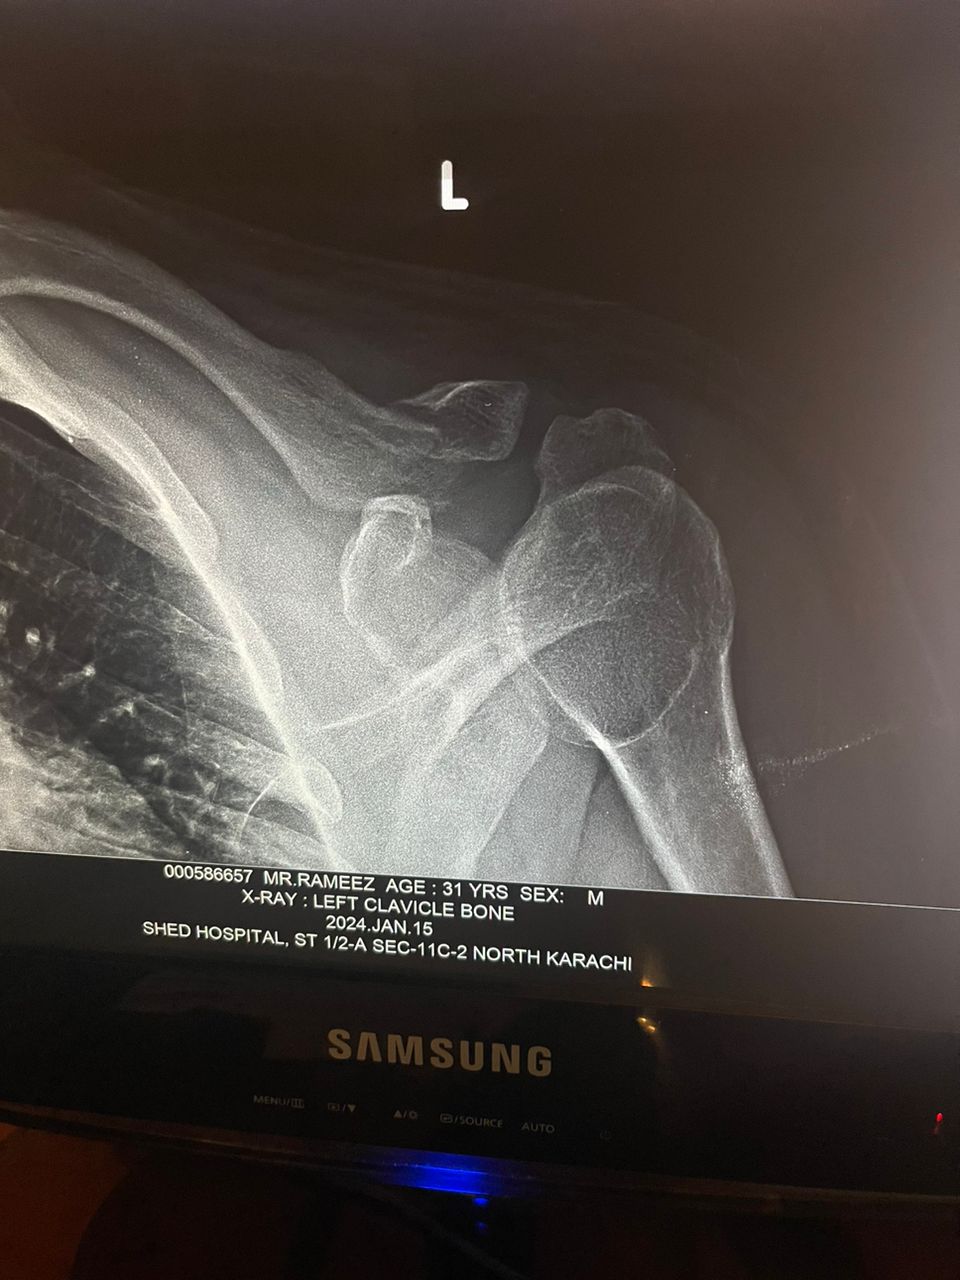

Talk to Orthopedic Surgeon on Left Clavicle Bone

Asking for Self, Male, 31 years old, Karachi

Got in to accident two days back, need advice on it.